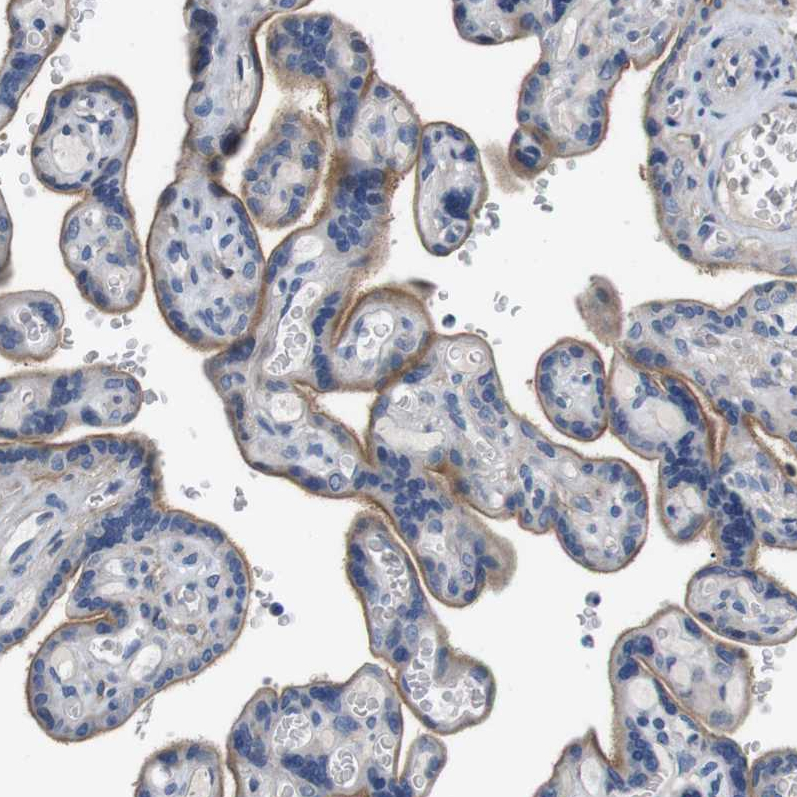

Immunohistochemical staining of human liver shows moderate membranous positivity in hepatocytes.